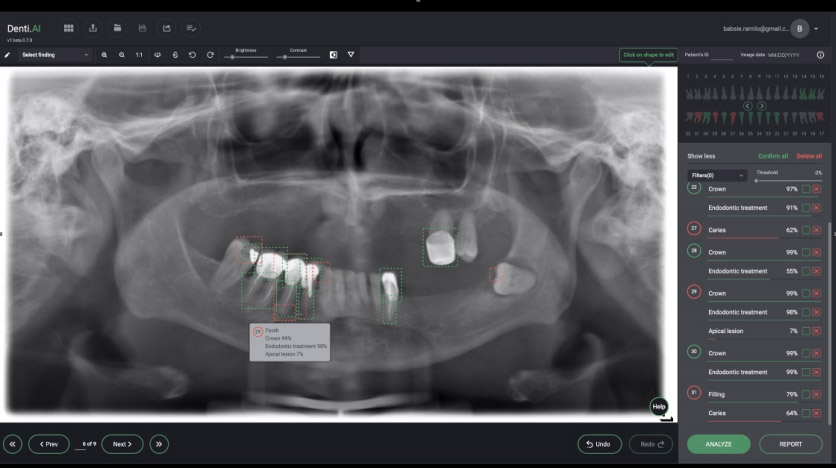

It appears that the broader introduction of AI into clinical dentistry will occur with interpretation of two-dimensional radiographs. Several start-up companies have developed systems to identify the anatomy, existing restorations and abnormal findings/pathology on bitewing and periapical films, as well as panoramic radiographs. (see Figures 2 and 3).

- Figure 3

These programs will scan radiographs, and can identify the anatomy [i.e., tooth number, crowns, cementoenamel junction, root length, distance from the cementoenamel junction (CEJ) to the crest of the alveolar bone], as well as abnormal/pathologic findings (i.e., periodontal disease as an indicated by increased distance from the CEJ to the alveolar crest, caries, the presence of a periapical radiolucency and root fractures). This identification can serve as an internal check on the clinician’s assessment of the radiographs, and it is claimed, thereby free up time to allow the dentist to spend more time with patients. From the perspective of large multi-practice organizations (i.e., dental service organizations), this technology can also enhance quality control across multiple offices. It is also expected that dental insurance companies will utilize this technology to assure that adequate documentation (quality of the radiographs) is provided, and determine if the request for benefits is within guidelines.

Figure 3. Panoramic radiograph analyzed by an AI system identifies deviations from normal. In this system deviations are listed by tooth number to the right. The percentages reflect the probability of that finding being present. Image courtesy of Dr. Eric Pulver (Denti.ai).